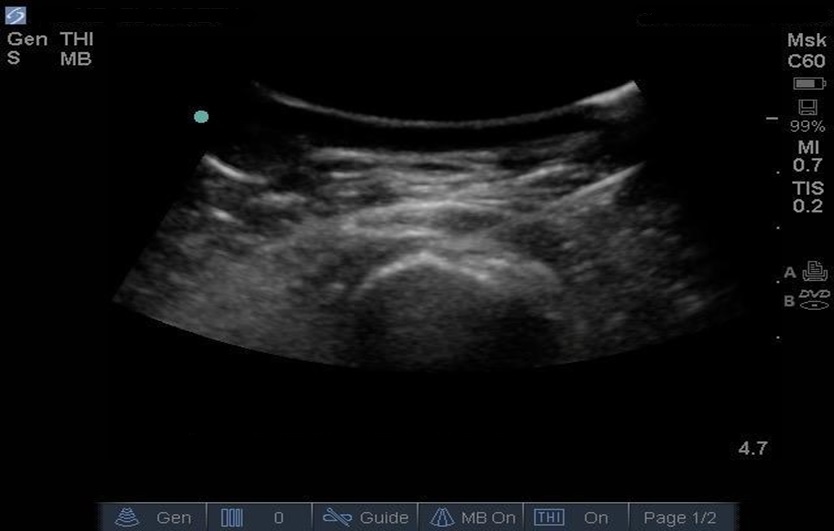

Cadera - Infiltración en bolsa trocantérica - Imagen